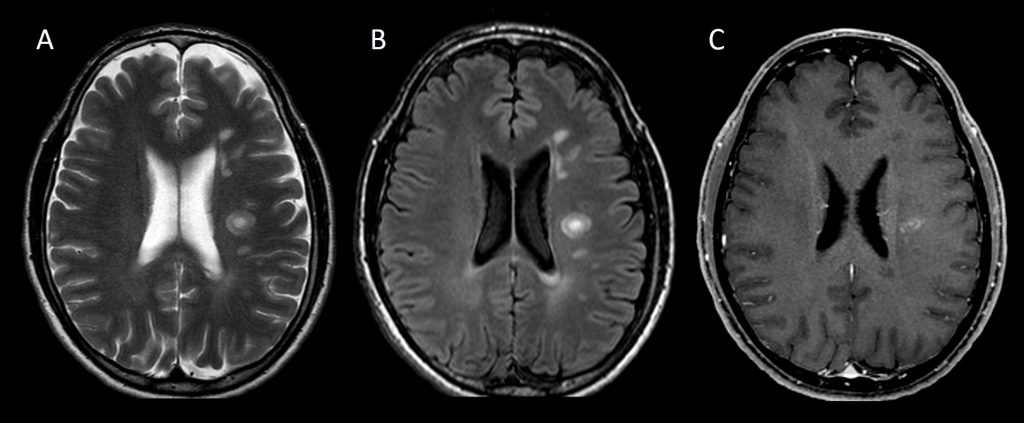

A. Imagen RM TSE T2 transversal.

B. Imagen RM FLAIR transversal.

C. Imagen RM EG T1 3D con supresión grasa tras administración de gadolinio iv.

Múltiples lesiones desmielinizantes ya conocidas de distribución supratentorial bilateral, periventricular y yuxtacortical. Se observa aparición de una nueva lesión desmielinizante en centro semioval izquierdo de 15 mm con morfología lamelar, sin edema circundante ni efecto masa significativo, que muestra realce en anillo incompleto con aspecto «en capas de cebolla».